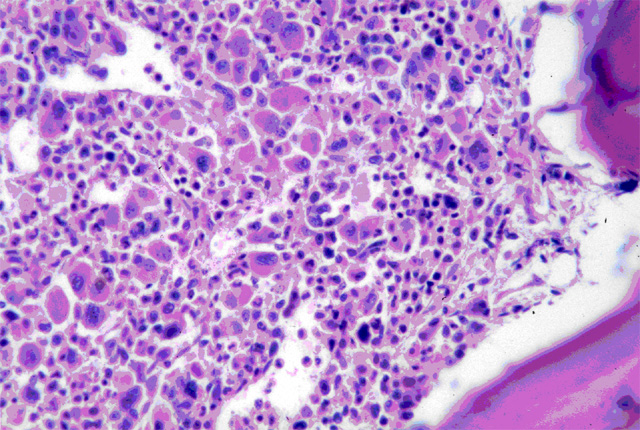

El 1º de abril se conmemora el Día Nacional del Donante de Médula Ósea celebrando los 11 años que cumple el Registro Nacional de Donantes de Células Progenitoras Hematopoyéticas del INCUCAI, Instituto Nacional Central Único Coordinador de Ablaciones e Implantes de la República Argentina. El hecho se convierte en una valiosísima oportunidad para invitar a todos los argentinos, que reúnen las condiciones exigidas, a inscribirse como donantes durante todo el mes de abril.Desde CUCAICOR en Corrientes los convocamos a sumarse a la Campaña “1000 Donantes de Médula Ósea en Corrientes” buscando promover la construcción de la especial solidaridad que la donación de médula ósea reclama al ser una donación de tejidos que ocurre en vida y pensando en personas que no conocemos. Estas personas están afectadas por enfermedades hematológicas como leucemia, anemia aplásica, linfoma, mieloma, errores metabólicos o déficits inmunológicos, que pueden ser tratadas con un trasplante de CPH, conocido popularmente como trasplante de médula ósea.